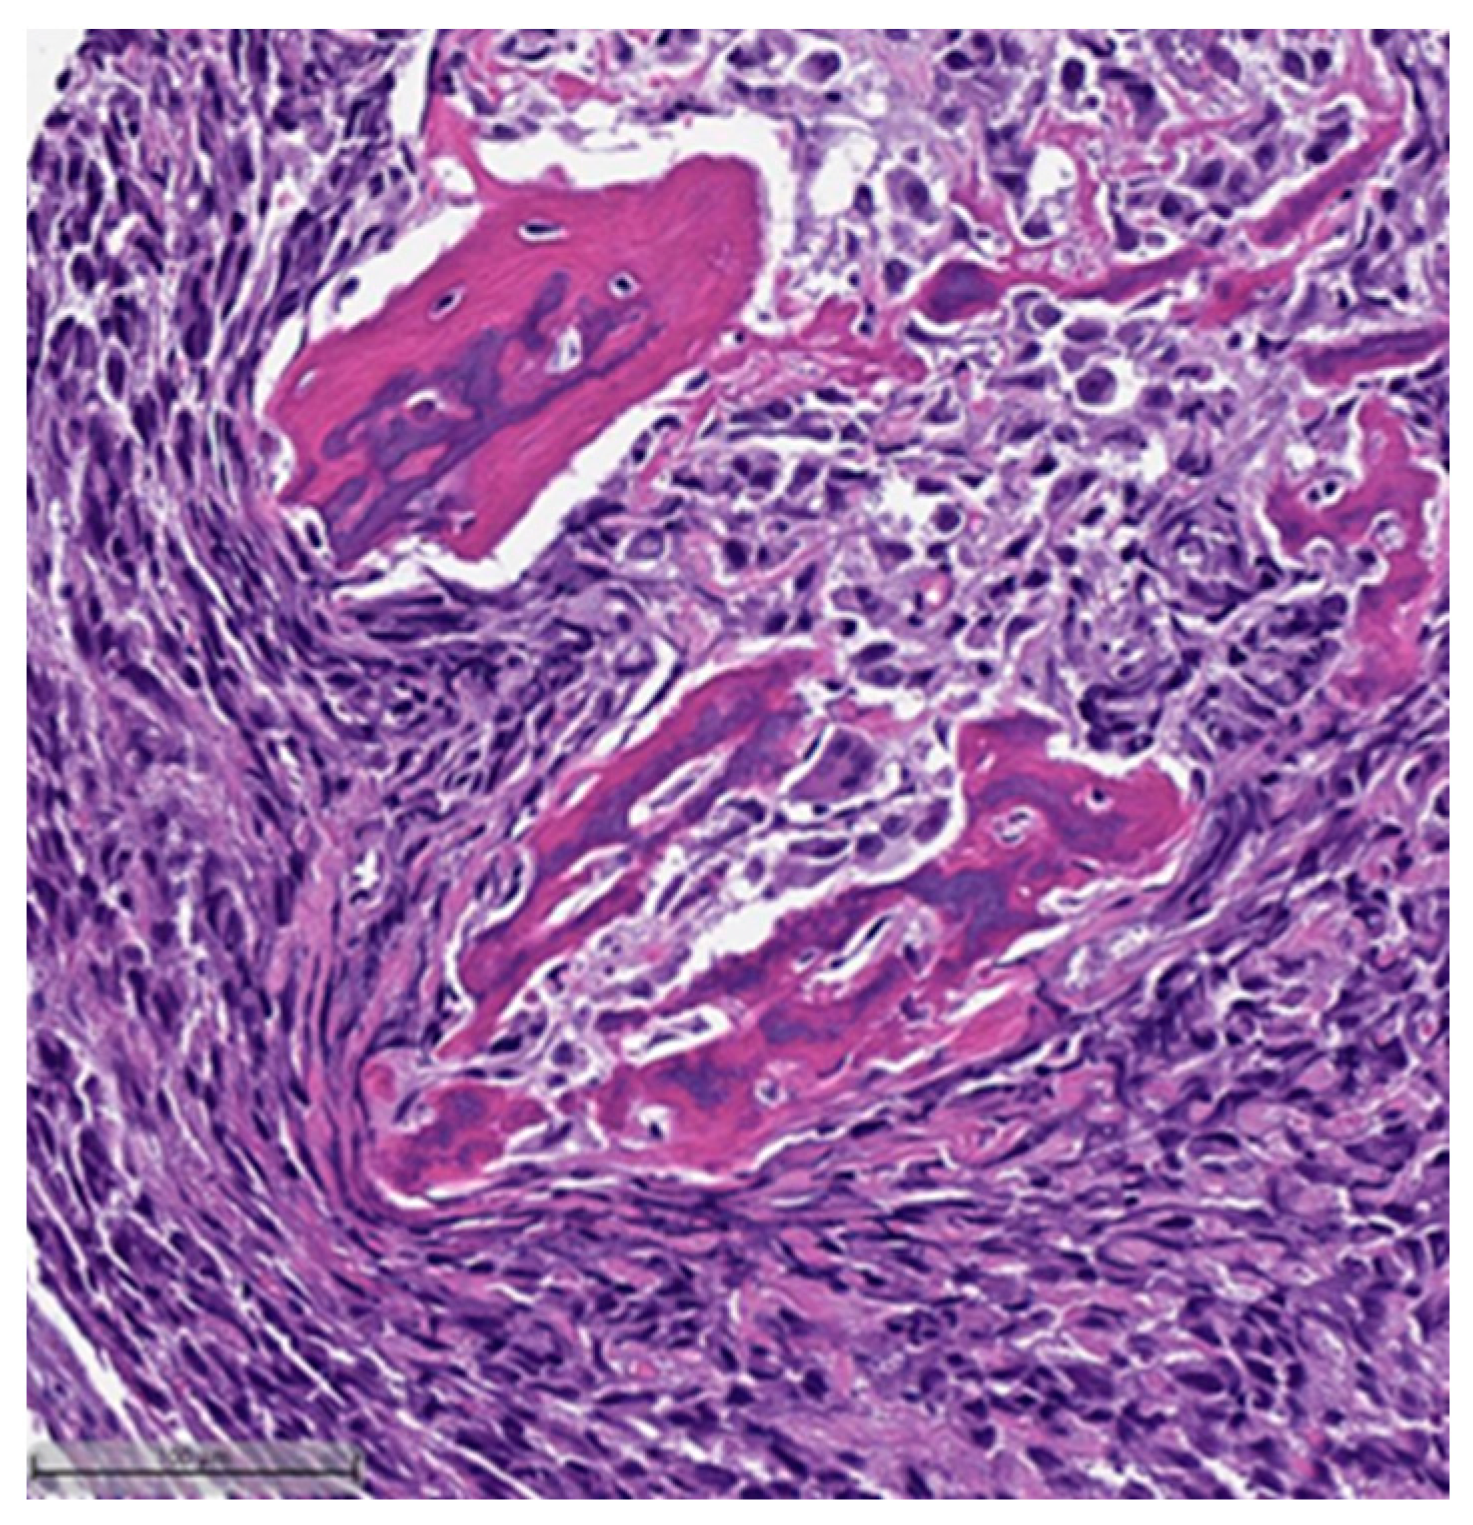

This system is primarily based on the specific metaplastic elements present within the tumors, while also highlighting the potential overlap that can exist between various histological subtypes [6]. Consequently, numerous cases diagnosed as MpBCs, are accompanied by a detailed description of the histological component or a combination of different component types and/or differentiations. The following figures illustrates a few examples: spindle cell carcinoma component with pleomorphic features (Figure 4), metaplastic breast carcinoma with chondroid differentiation (Figure 5), metaplastic breast carcinoma with a matrix-producing component (Figure 6), metaplastic breast carcinoma with osseous differentiation (Figure 7), and extensive trabeculae bone and hematopoietic tissue (Figure 8).

Figure 5.

Metaplastic breast carcinoma with chondroid differentiation (H&E, 20×).

Figure 7.

Metaplastic breast carcinoma with osseous differentiation (H&E, 20×).

Figure 8.

Same case in Figure 7: showing extensive obvious bone trabeculae and hematopoietic tissue (H&E, 20×).